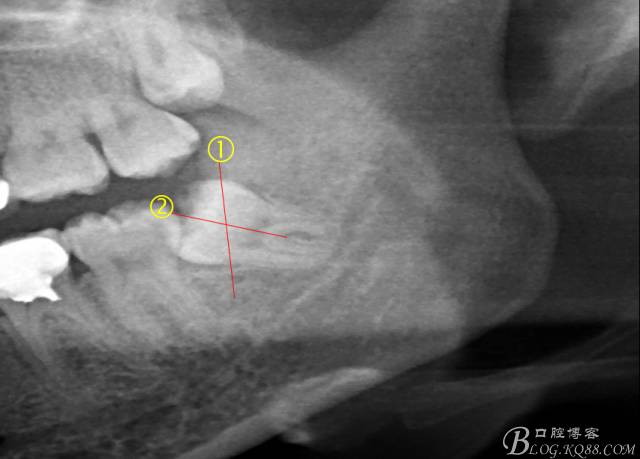

X全景片示38近中三類阻生,非融合根,近中根壓下頜管,37遠(yuǎn)中鄰面中齲樣影像。

先分析智齒的情況,口內(nèi)直觀是半個(gè)牙尖都沒露出來,差一點(diǎn)就完全埋伏了。磨牙后墊的可操作面積中規(guī)中紀(jì),X全景片示三類阻生,根冠比例是1:1,非融合根,近中根壓下頜管。

術(shù)前分析:智齒分牙的方法不少,但個(gè)人感覺都與這十字分牙法差不多,大多數(shù)阻生齒的分牙都在此基礎(chǔ)上進(jìn)行改進(jìn)。